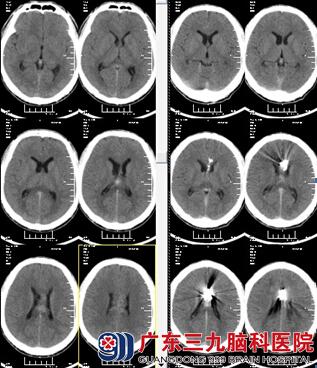

温先生正在上班时候突发头痛、呕吐,随后昏迷,只能发声不能睁眼。同事将温先生送到广东三九脑科医院就诊,头颅CTA示:胼胝体动静脉畸形;双侧脑室内出血;既往史:2009年曾因脑出血治疗,当时诊断为动静脉畸形,具体家属无法提供。

因病情紧急,由林涛主任主刀急诊全麻下为行“脑室外引流术”,术程顺利,术后予以预防感染、止血、脱水、支持、对症等综合治疗,2周后温先生意识逐渐好转。行全脑血管造影术,影像显示:左胼胝体区动静脉畸形;由于畸形较大,一次栓塞术难以处理,需分次进行。告知术中、术后相关风险后,家属表示理解并同意手术后行胼胝体体部动静脉畸形栓塞术,术程顺利,复查造影见动静脉畸形栓塞共约90%。术后复查头颅CT示:呈栓塞术后改变,未见新鲜出血。温先生康复出院。